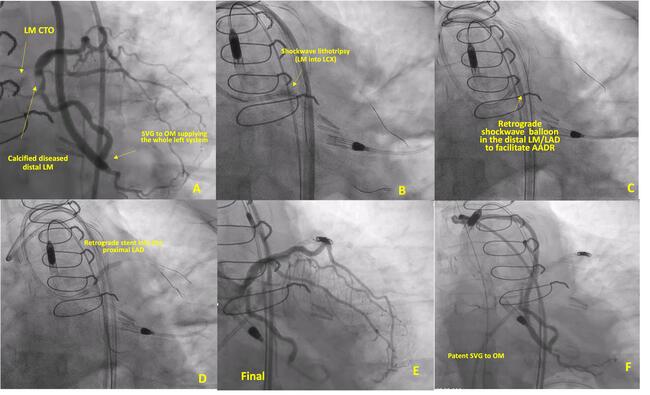

A 72-year-old woman presented with progressive angina and anterior ischemia on a nuclear stress test. She had a history of previous bypass graft surgery with an atretic left internal mammary artery graft (LIMA) to the left anterior descending artery (LAD) and patent vein grafts to the right coronary artery (RCA) and the obtuse marginal branch (OM). The left main coronary artery (LM) was heavily calcified and chronically occluded, and the distal LM was severely calcified (Figure 1A; Videos 1, 2). The decision was made to proceed with LM CTO PCI.

Right heart catheterization showed normal hemodynamics. We inserted an Impella CP (Abiomed) through the left femoral artery due to the risk of hemodynamic compromise with the retrograde approach through the only graft supplying the left system. We placed two 8 French 45-cm long sheaths through the right femoral artery. Multiple antegrade attempts failed. Multiple retrograde attempts failed due to the blunt distal cap and the difficult angle of penetration. Eventually, an Astato 20 (Asahi Intecc) wire crossed into the left circumflex artery (LCX). We used Shockwave lithotripsy balloon angioplasty from the LM into the LCX in an attempt to fracture the calcium at the distal LM to facilitate reentry into the LAD, but this also failed (Figure 1B, Video 3). We attempted the antegrade antegrade dissection re-entry technique (AADR)2 by inflating regular and cutting balloons placed retrogradely into the LAD and attempting to puncture towards it, but this also failed. Lithotripsy performed retrogradely over a Grand Slam wire (Asahi Intecc) also failed to facilitate AADR (Figure 1C, Figure 2A).

We delivered a stent retrogradely to the LAD delivered as a target for the antegrade wire (stent target technique) (Figure 2B). We deployed a 3-mm stent into the proximal LAD over the retrograde wire (Figure 1D, Video 4). We then crossed from the LM into the LAD stent and performed intravascular ultrasound (IVUS)-guided PCI of the LM to the LAD (Figure 1E). We detected a perforation of a small diagonal branch coiled with multiple Interlock coils (Boston Scientific). Final images showed excellent Thrombolysis in Myocardial Infarction (TIMI) 3 flow from LM into the LAD (Figure 1F, Video 5) and patent saphenous vein grafts (SVG) to the OM (Video 6). We removed the Impella CP device after 36 hours and closed the site with the MANTA device (Teleflex). The patient was doing well at the 6-month follow-up.